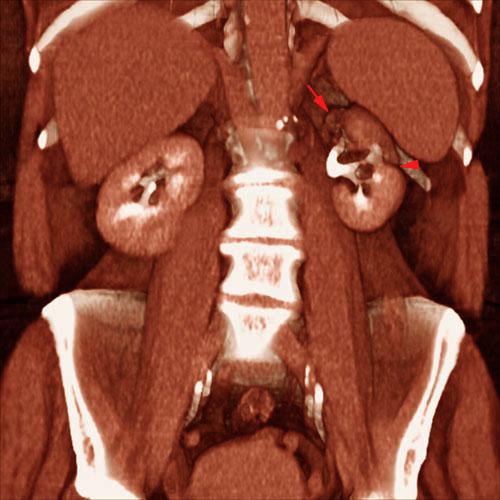

Pielonefritis crónica

VR seccional. Visión coronal anterior. Exploración contrastada en fase excretora. Existe una atrofia cortical del polo renal superior izquierdo (flecha) y una lesión cicatrizal cortical (punta de flecha) con disminución de la distancia corticomedular